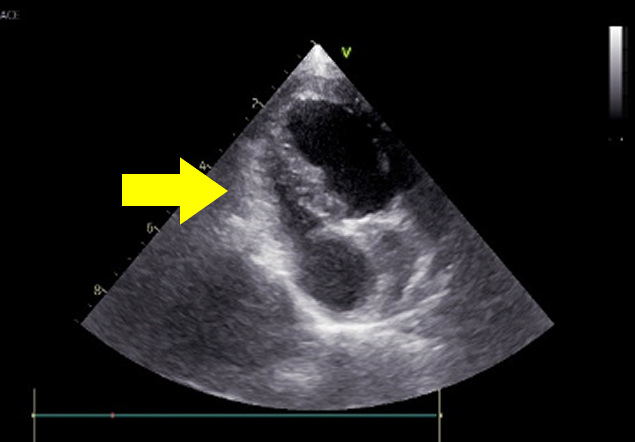

診断は身体検査、超音波検査、レントゲン検査、血圧測定、心電図、血液検査などにより総合的に行います。治療は心臓の負荷を軽減する薬による治療が一般的です。一部施設では手術による治療も行われています。(手術をご希望の方は施設をご紹介いたします)